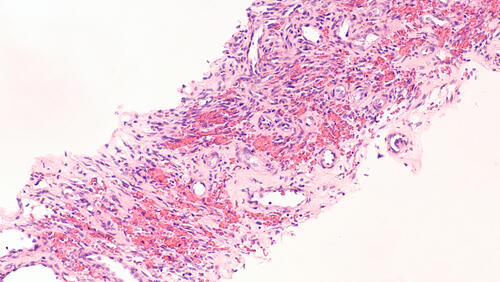

The patient, a 37-year-old HIV-negative man, presented with a painful 1.5 x 1.3 cm mass on the plantar second digit. The granuloma had increased in size and was resistant to antibiotics and wound care. The authors note the initial punch biopsy indicated pyogenic granuloma.

Due to the pain, the patient had the granuloma excised. Pathology of a tissue specimen later indicated the mass was Kaposi sarcoma, according to the poster. The authors emphasize that Kaposi sarcoma can be difficult to distinguish from pyoderma gangrenosum clinically and pathologically, and stress the importance of immunostaining and ascertain a thorough patient history.